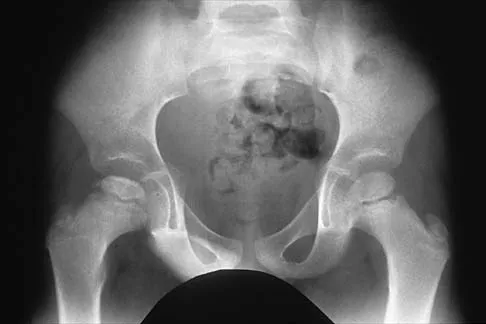

A 12-year-old boy reports the acute onset of pain and a pop over the right side of his pelvis while swinging a baseball bat during a Little League game. Radiographs reveal an avulsion of the anterior superior iliac spine with 2 cm of displacement. Management should consist of